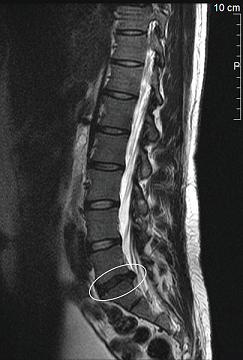

Nicht jeder Rückenschmerz ist gleich ein Bandscheibenvorfall